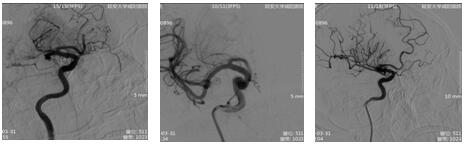

17:21 DSA示:右側大腦中動脈、前動脈閉塞。與患者家屬談話,簽字后立即行中動脈、前動脈取栓術。

18:55 術后患者神經(jīng)功能及肢體功能逐漸恢復,意識轉清,上肢肌力4級,下肢肌力3級。卒中中心又成功救治一名危重患者。這是一場與時間的賽跑,更是一場與死神的搏斗。